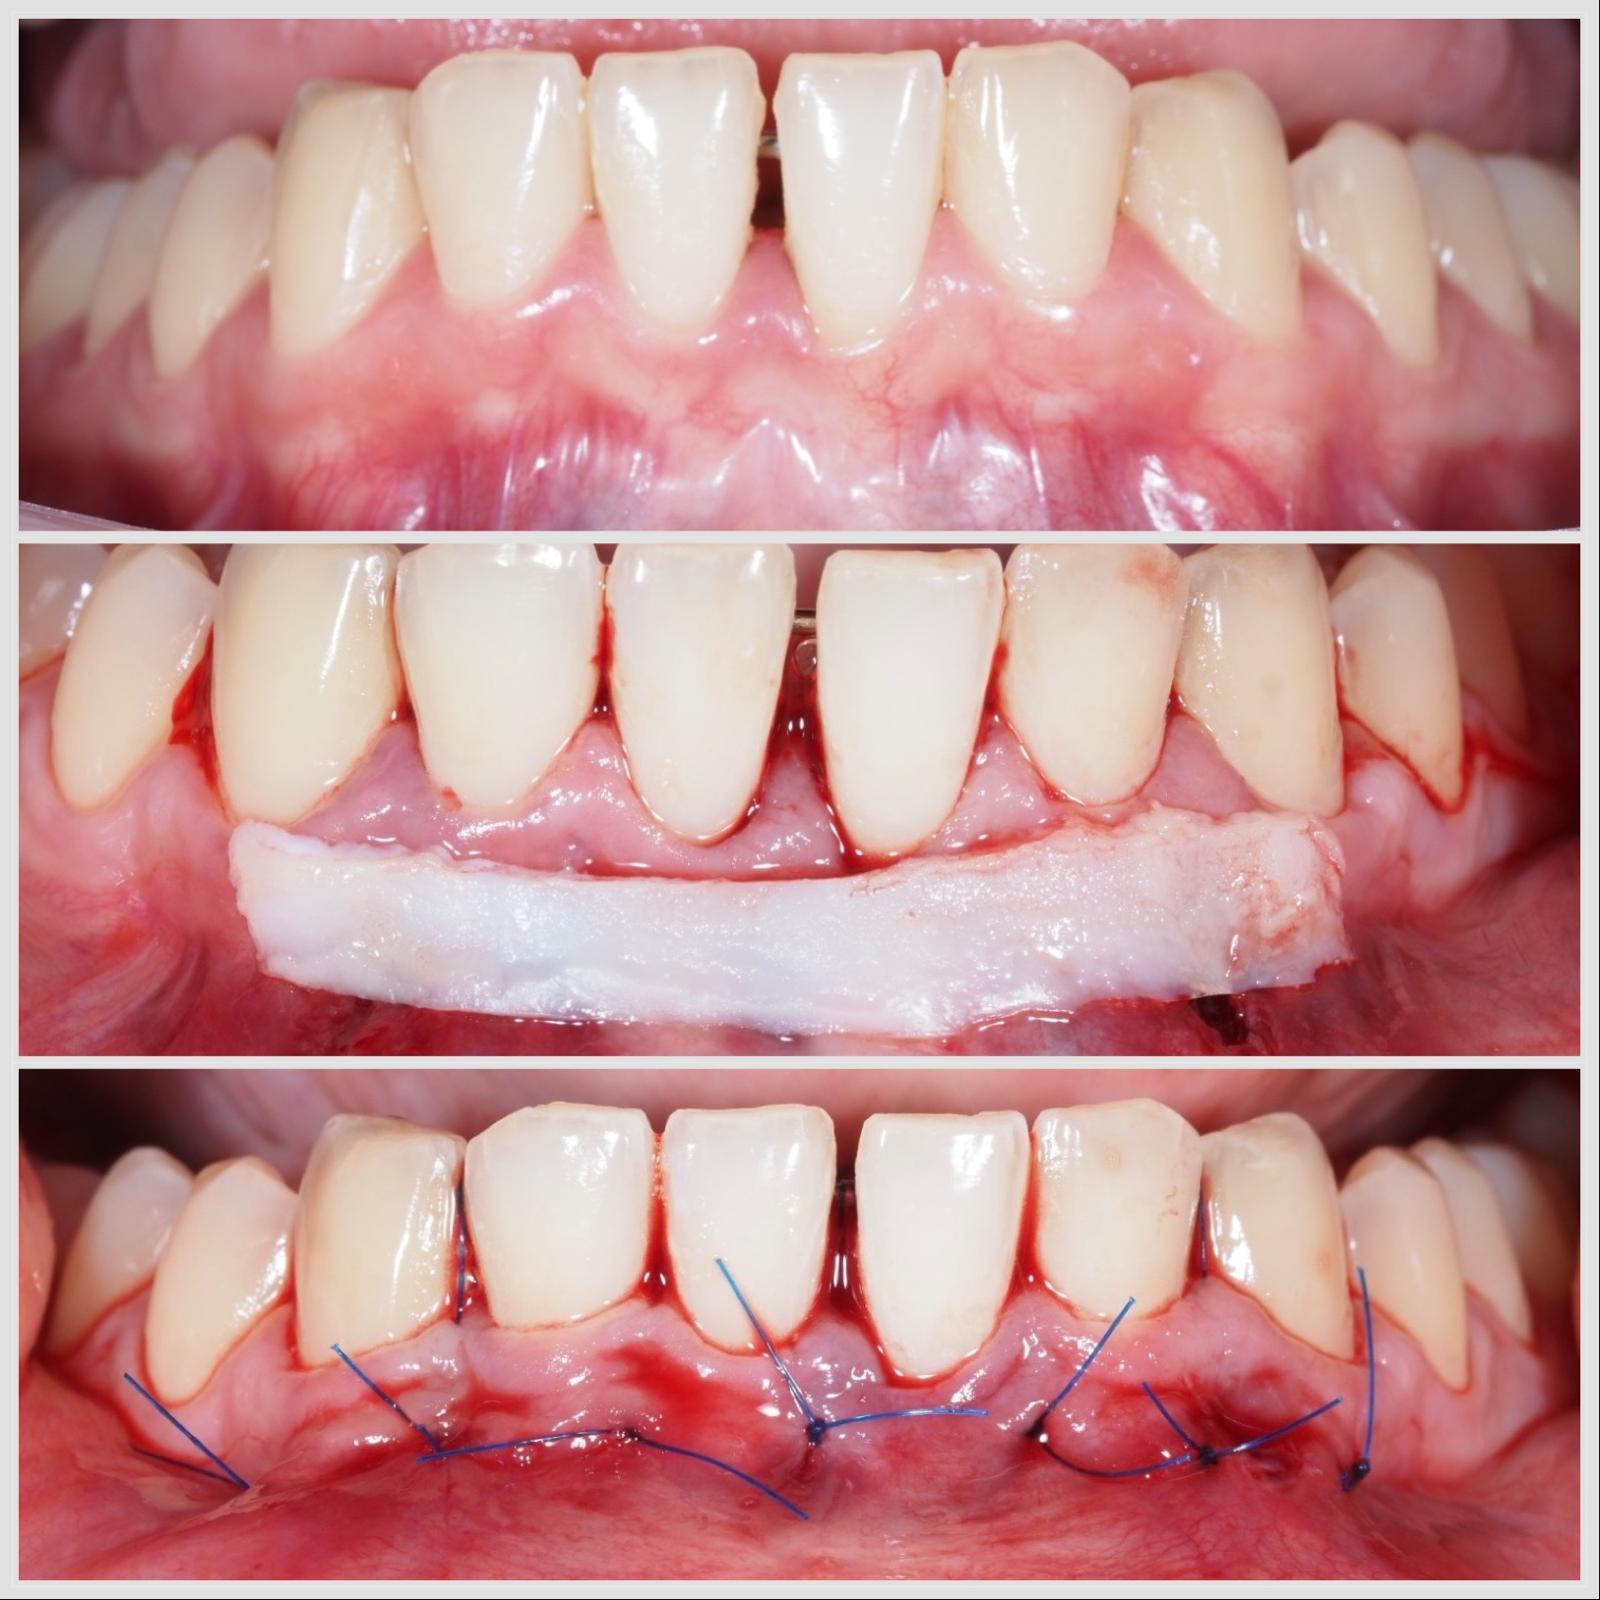

Greffe conjonctive réalisée par technique tunnelisée pour traiter une récession gingivale à Apolline Dental Care à Corbeil-Essonnes

Greffe Conjonctif

Greffe conjonctive mandibulaire réalisée par technique tunnelisée pour traiter une récession gingivale à Apolline Dental Care à Corbeil-Essonnes

Greffe conjonctive réalisée par tunnel mandibulaire pour régénération naturelle des gencives à Apolline Dental Care à Corbeil-Essonnes